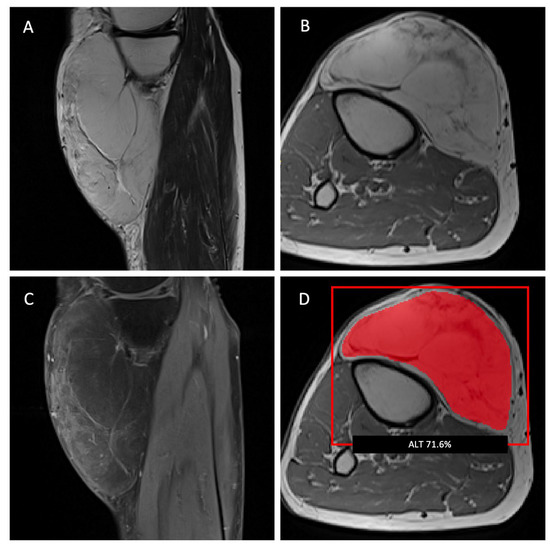

2.2. MR Imaging Protocol and Image Segmentation

2.3. Radiomic Feature Extraction and Machine-Learning Model Development